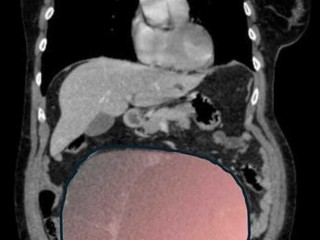

Il caso, definito dai medici un evento “normalmente eccezionale”, è stato preso in carico dalla Chirurgia Ginecologica mininvasiva dell’ospedale Sant’Anna di Torino, diretta dal dottor Paolo Petruzzelli. Nonostante le festività imminenti, la macchina della sanità piemontese si è attivata con una rapidità straordinaria: il 23 dicembre la paziente è stata sottoposta a un intervento durato sei ore che ha visto l’asportazione di una massa di ben 6 chilogrammi e un diametro di 28 centimetri.